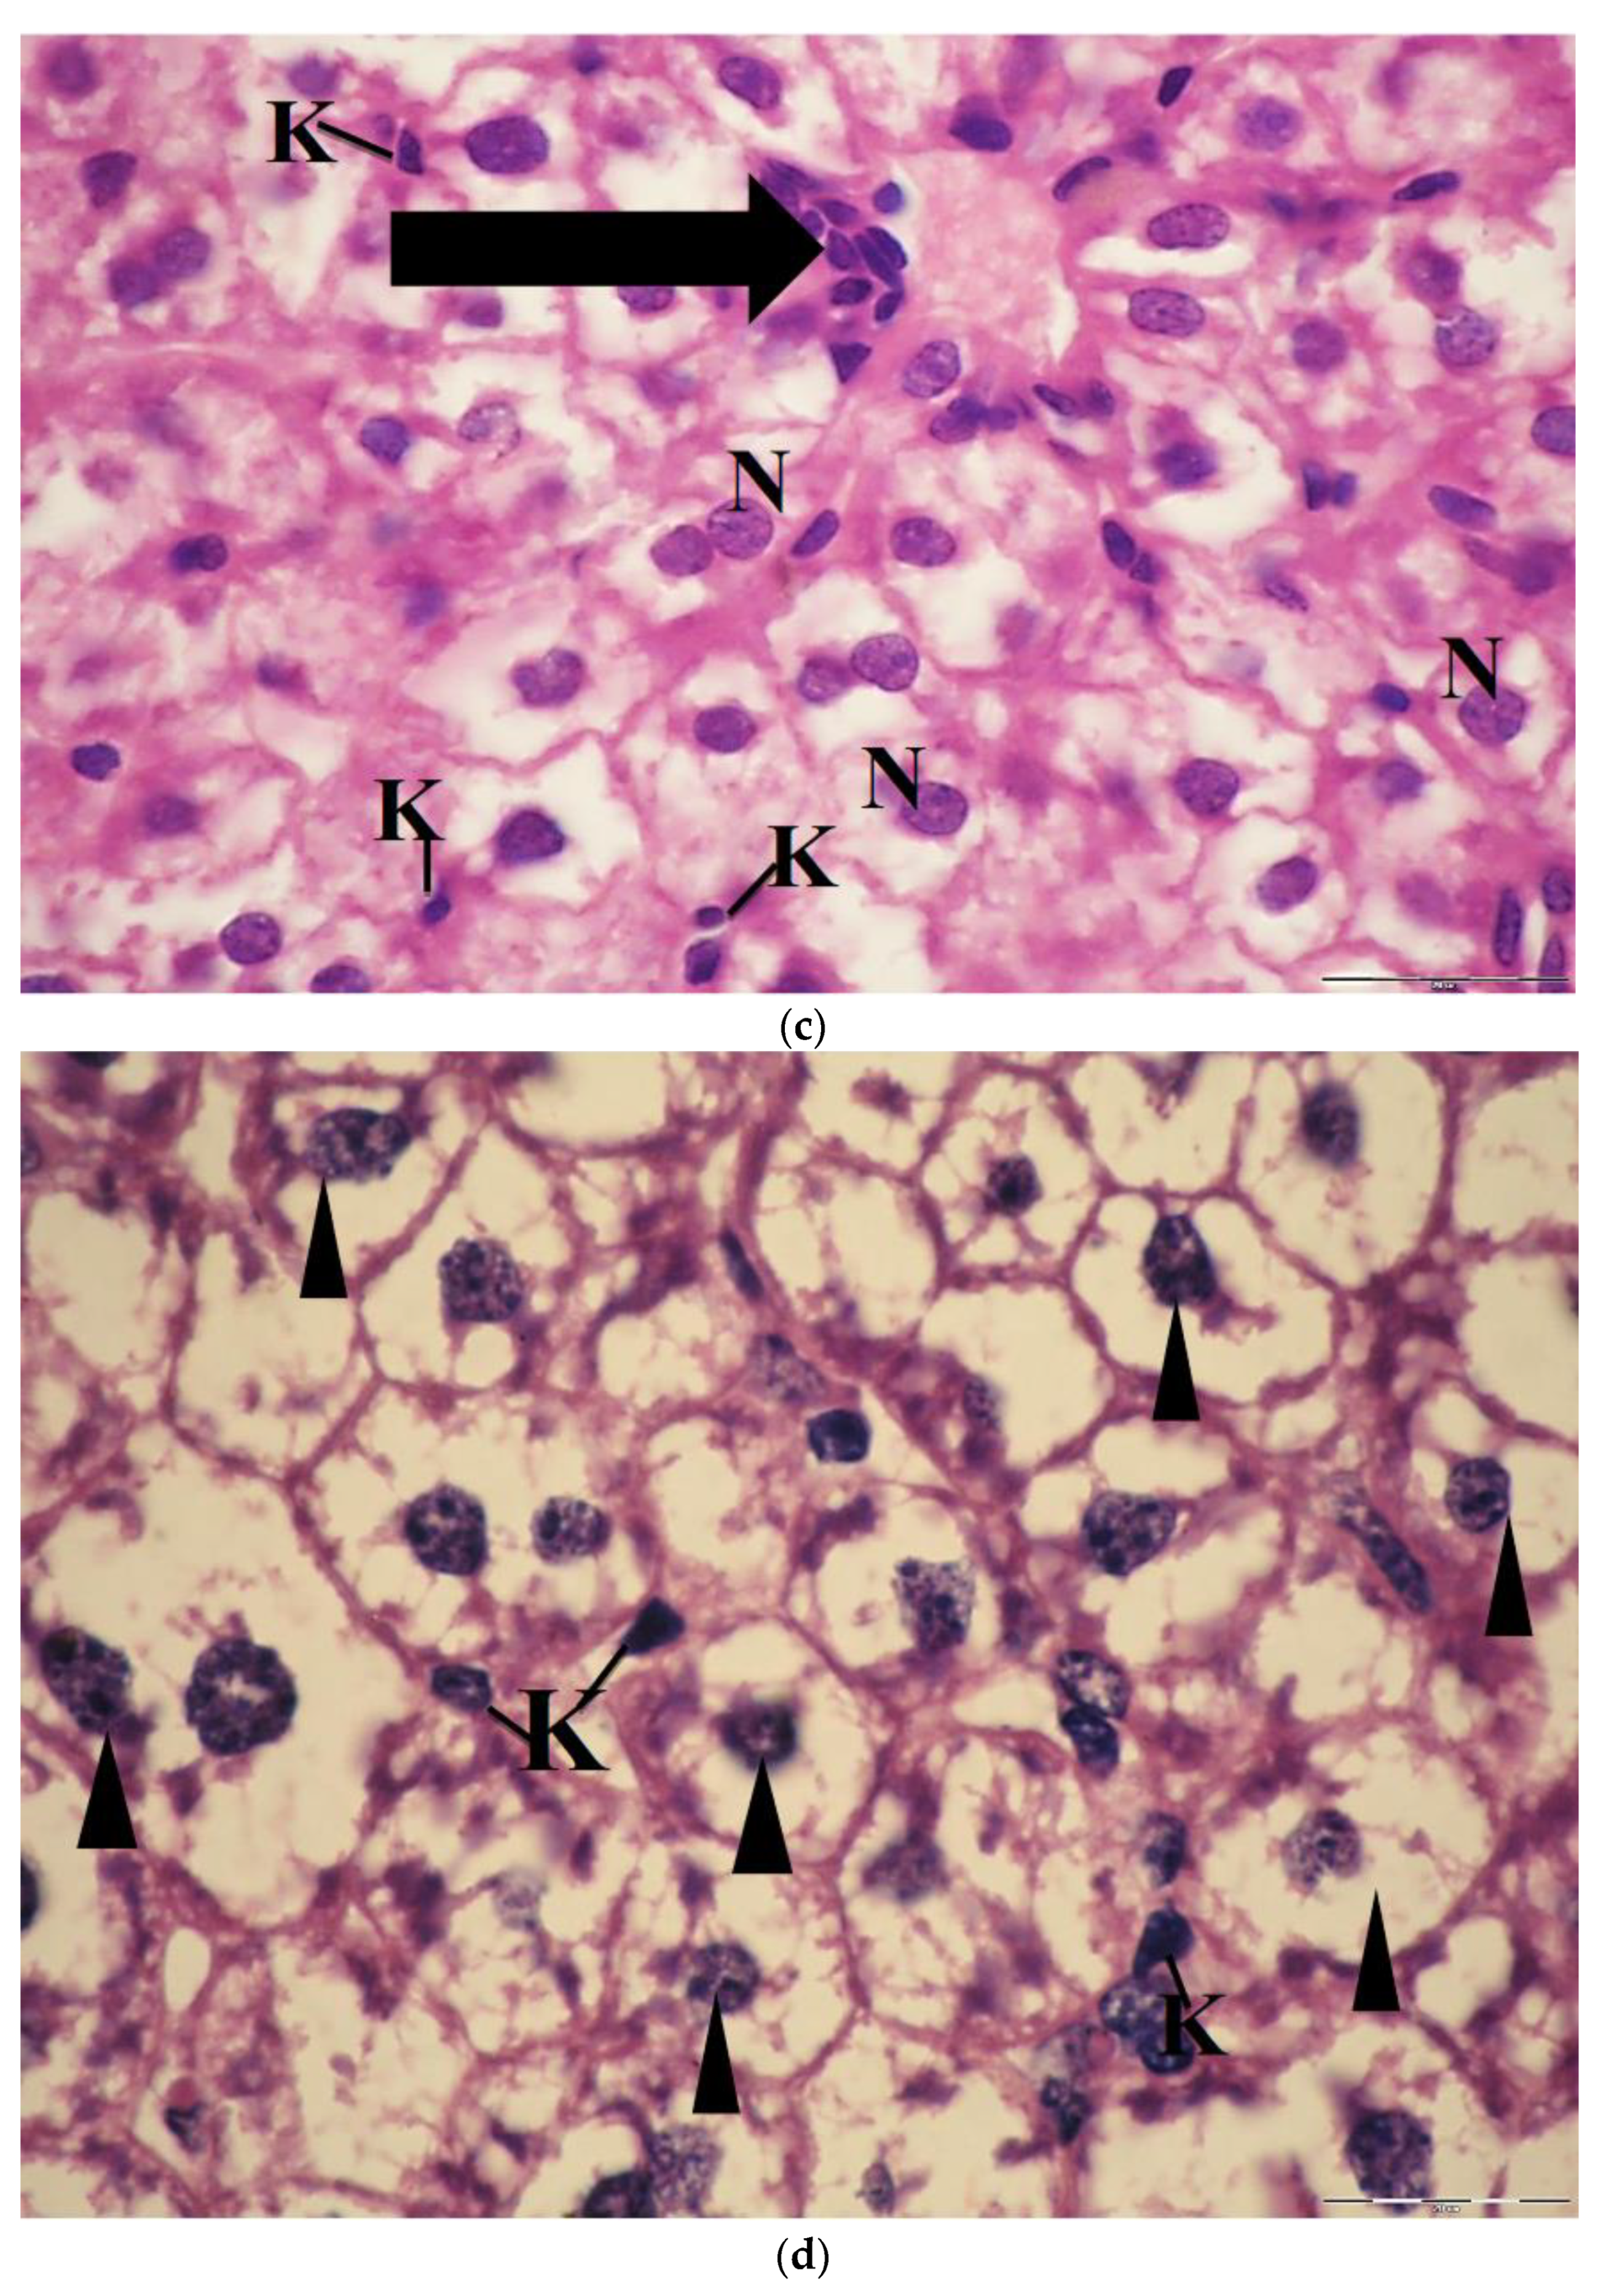

2.6. Light Microscopic Observations

The liver of control mice revealed that the hepatocytes are polygonal in shape and exhibited distinct boundaries, and they have centrally located spherical or ovoid basophilic nuclei and acidophilic cytoplasm. These nuclei showed considerable variations in size from cell to cell. Each nucleus contains one or two prominent nucleoli and dispersed chromatin (Figure 8a). The light micrographs of liver mice treated with 60 mg/kg of ESE showed that the hepatocytes had preserved their characteristic organization and became separated from each other by wide sinusoidal spaces. Their nuclei were vesicular and displaying normal appearance. The activated Kupffer cells were observed in most liver sections of the tissue (Figure 8b).

Sections of liver mice treated with 100 mg/kg CuNPs showed that the hepatocytes were more or less similar to the control. In a few sections, they had lost their characteristic organization, and the cytoplasm was slightly vacuolated. The nuclei were vesicular and displaying their normal shaped structures. Kupffer cells appeared few and showing a marked decrease in their sizes (Figure 8c). However, the light micrographs of liver sections of mice administered with 250 mg/kg CuNPs showed severe congestion and dilatation of the blood vessels, in addition to the massive lymphocytic infiltration around them. Most of the hepatocytes were greatly damaged, exhibiting severe vacuolation, and had lost their acidophilic substances. Moreover, the nuclei in most hepatocytes were displaying pyknosis, and few small-sized Kupffer cells were observed (Figure 8d).

Furthermore, the hepatocytes in sections of liver mice treated with 100 mg/kg CuNPs + 60 mg/kg ESE showed no evidence of damage compared to those treated only with 100 mg/kg CuNPs. However, an observable dilatation in the hepatic sinusoids was seen (Figure 8e). The light micrographs of liver mice treated with 250 mg/kg CuNPs and 60 mg/kg ESE showed that the hepatocytes normally appeared in their polygonal-shaped structure. Their nuclei were vesicular and displaying their normal shaped structures as well as the control. The Kupffer cells were normal in shape (Figure 8f).

In the current study, the cytotoxicity of CuNPs was evidenced by the appearance of morphological changes in liver cells, such as congestion and dilatation of the blood vessels, the presence of much inflammatory infiltration in pre-central veins, as well as the appearance of hepatocellular necrosis. These alterations were prominent in the liver tissues of mice administered with 250 mg/kg of CuNPs. However, the decrease in these degenerative changes in the liver of mice was apparent in the liver tissues of mice treated with ESE. Our present study, parallel with Kim et al. [46], reported some histopathological changes and increased infiltration around the central vein induced by nanoparticles. The destruction of lobular structure and vacuolization of hepatocytes together with the dilatation of the central vein and blood sinusoids indicate that these NPs may affect the permeability of the cell membrane in hepatocytes and the endothelial lining of blood vessels [66]. Additionally, the appearance of inflammatory cells in hepatic tissue suggests that nanoparticles can interact with proteins and enzymes in the interstitial tissue of the liver, interfering with the antioxidant defense mechanism and leading to the generation of ROS, which in turn may induce an inflammatory response [67].

The obtained results are consistent with the previous findings of Doudi and Setorki [19] who found that 100 mg/kg CuNPs induced histological changes in the hepatic tissues, vasculature in the central vein, and the disappearance of hexagonal liver lobules which is lined with the present study. Moreover, the destruction of the lobular structure, vacuolization of hepatocytes (fat deposits), and congestion of RBC, and infiltration of leukocytes in the liver tissue of mice administered with 300 mg/kg ZnNPs, indicating its necrotic effects [56].

Figure 8. (a) Light micrograph of mice liver of control group showing, the vesicular spherical nuclei (N), binucleated hepatocytes (arrow); hepatic sinusoids (S); triangular-shaped Kupffer cells (K), H&E, ×1000. (b) Light micrograph of liver mice treated with 60 mg/kg bw of ethanolic saffron extract, showing polygonal hepatocytes (H); vesicular nuclei (N); wide blood sinusoids (S); many activated Kupffer cells (K), H&E, ×1000. (c) Light micrograph of liver mice treated with 100 mg/kg bw of CuNPs showing vacuolated hepatocytes; nuclei (N); few leucocyte infiltrations (thick arrow) and small size Kupffer cells (K), H&E. ×1000. (d) Light micrograph of liver mice treated with 250 mg/kg bw of CuNPs showing degeneration and vacuolated hepatocytes; pyknotic nuclei (arrowheads); Kupffer cells (K), H&E, ×1000. (e) Light micrograph of liver mice treated with 100 mg/kg bw of CuNPs + 60 mg/kg bw ethanolic saffron extract showing polygonal-shaped hepatocytes containing vesicular nuclei (N). Note: dilated blood sinusoids (S) and few small-sized appearances of Kupffer cells (K), H&E, ×1000. (f) The light micrographs of liver mice treated with 250 mg/kg bw of CuNPs + 60 mg/kg bw ethanolic saffron extract showed vacuolated hepatocytes (H) with vesicular nuclei (N) and Kupffer cells (K), H&E, ×1000.